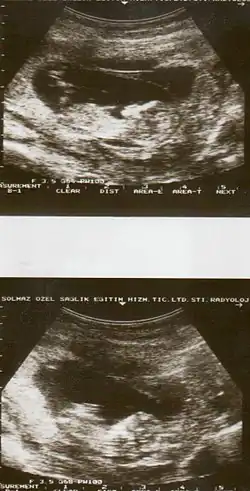

Diagnostic method | Based on symptoms, ultrasound[1] |

The cause of placental abruption is not entirely clear.[2] Risk factors include smoking, pre-eclampsia, prior abruption (the most important and predictive risk factor), trauma during pregnancy, cocaine use, and previous cesarean section.[2][1] Diagnosis is based on symptoms and supported by ultrasound.[1] It is classified as a complication of pregnancy.[1]

Placental abruption is suspected when a pregnant mother has sudden localized abdominal pain with or without bleeding. The fundus may be monitored because a rising fundus can indicate bleeding. An ultrasound may be used to rule out placenta praevia but is not diagnostic for abruption.[8] The diagnosis is one of exclusion, meaning other possible sources of vaginal bleeding or abdominal pain have to be ruled out in order to diagnose placental abruption.[5] Of note, use of magnetic resonance imaging has been found to be highly sensitive in depicting placental abruption, and may be considered if no ultrasound evidence of placental abruption is present, especially if the diagnosis of placental abruption would change management.[16]